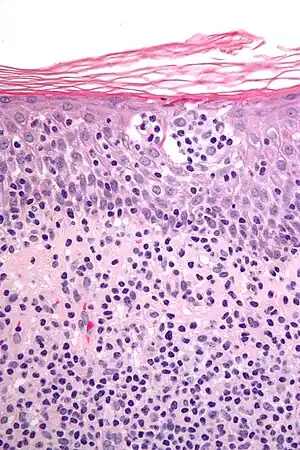

| Micrograph showing cutaneous T-cell lymphoma. H&E stain | |